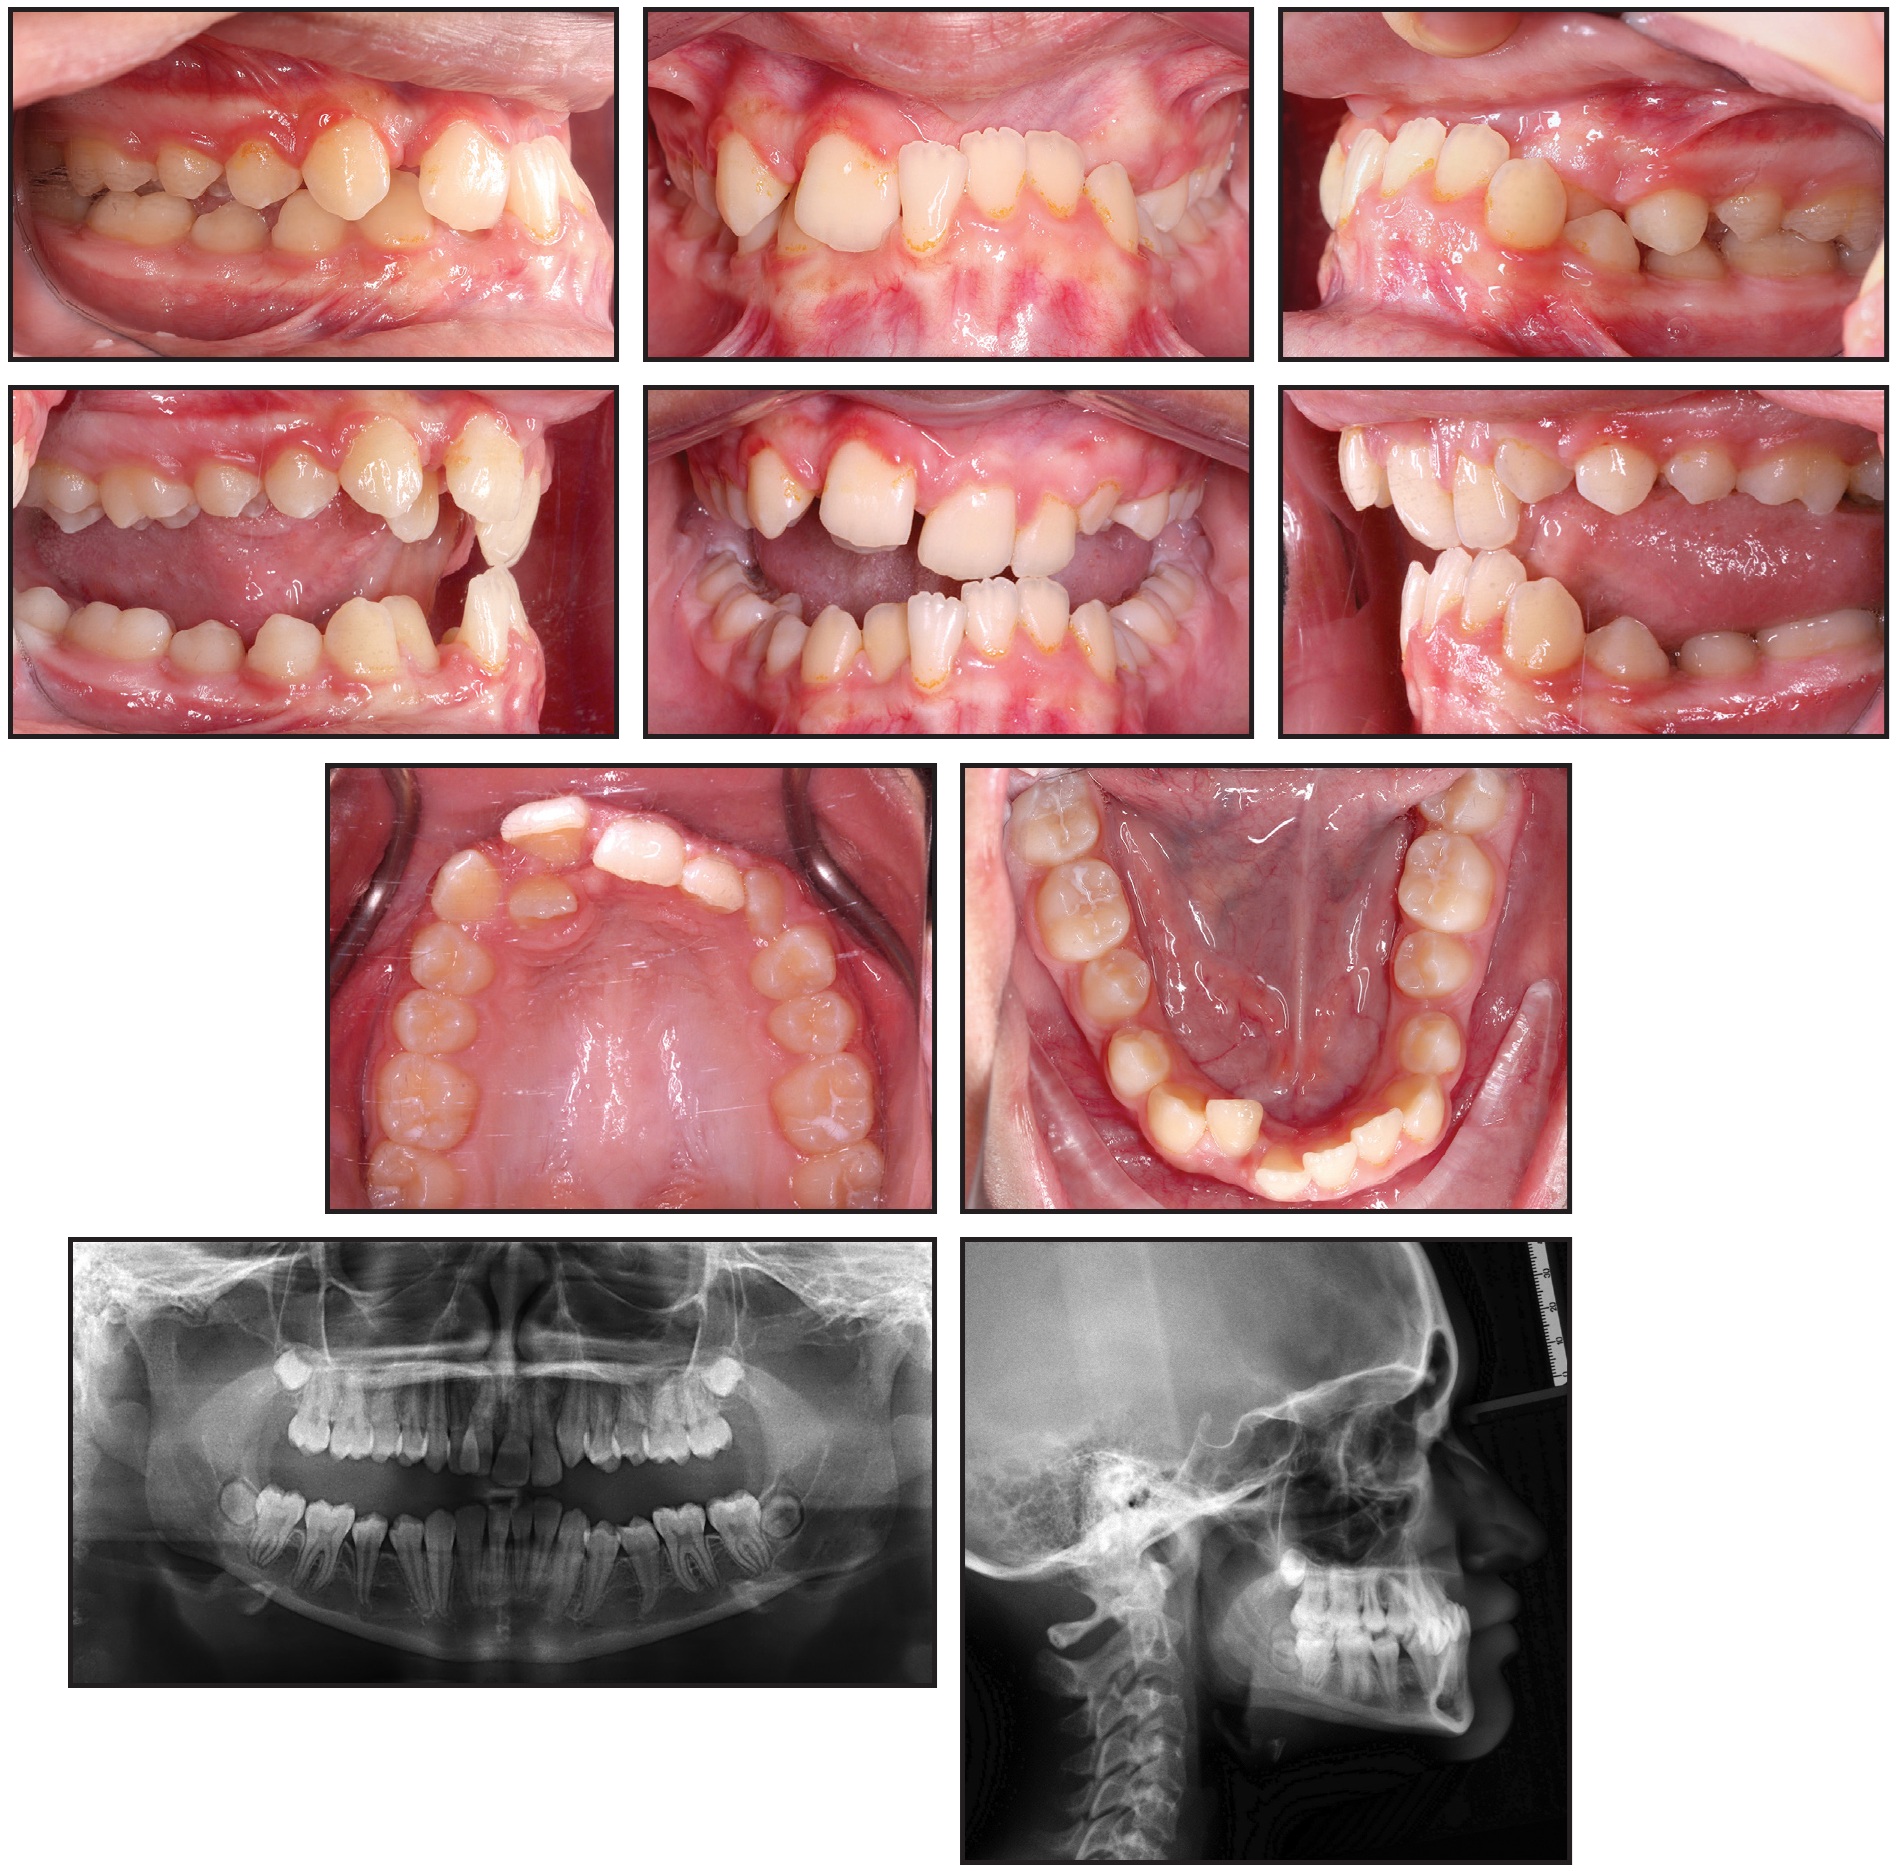

DIAGNOSTIC CHALLENGE #1

Part 1

In this monthly column, Contributing Editors Gayle Glenn, DDS, MSD, and Shawn L. Miller, DMD, MMSc, present a case to challenge your diagnosis and treatment-planning skills. Review the initial records below, and go to the comments section at the bottom of the page to share your thoughts. In the next issue, Dr. Glenn and Dr. Miller will discuss how the case was treated.

Courtesy of University at Buffalo

Click for larger views of Figure A and Figure B.

Fig. A

Fig. B